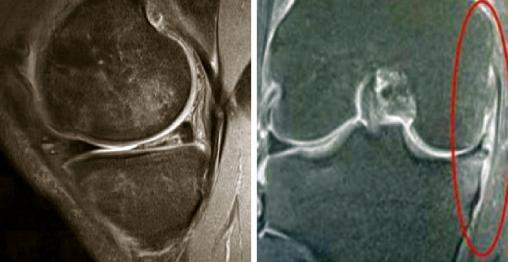

Lésion complexe avec extrusion méniscale (pré-arthrose).

Extrait de : Item 357 - Lésions péri-articulaires et ligamentaires du genou, de la cheville et de l'épaule